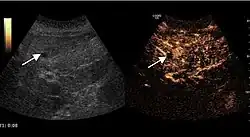

US examination is required to detect liver metastases in patients with oncologic history. In addition, the method can incidentally detect metastases in asymptomatic patients. Early identification (small sizes, small number) is important to establish an optimal course of treatment which can be complex (chemotherapy, radiofrequency ablation, surgical resection) but welcomed. In addition, discrimination of synchronous lesions that have a different nature is also important knowing that up to 25–50% of liver lesions less than 2 cm detected in cancer patients may be benign . US sensitivity for metastases detection varies depending on the examiner's experience and the equipment used and ranges between 40 and 80% . Sensitivity is conditioned by the size and acoustic impedance of the nodules. For a lesion diameter below 10 mm US accuracy is greatly reduced, reaching approx. 20%. Other elements contributing to lower US performance are: excessive obesity, fatty liver disease, hypomobility of the diaphragm, and certain patterns of hyperechoic or isoechoic metastases that can be overlooked or can mimic benign conditions. Conventional US appearance of metastases is uncharacteristic, consisting of circumscribed lesions, with clear, imprecise or "halo" delineation, with homogeneous or heterogeneous echo pattern. They can be single (often liver metastases from colonic neoplasm) or multiple. Echogenity is variable. When increased, they can compress the bile ducts (which may be dilated) and the liver vessels. Liver involvement can be segmental, lobar or generalized. In this situation a pronounced hepatomegaly occurs. Generally, metastases have non-characteristic Doppler vascular pattern, with few exceptions (carcinoid metastases). Cyst-adenocarcinoma metastases due to semifluid content may have a transonic appearance. When increasing, they can result in central necrosis. CEUS examination is a real breakthrough for detection and characterization of liver metastases.

Increased performance is based on identifying specific vascular patterns during the arterial phase and seeing metastases in contrast to normal liver parenchyma during the sinusoidal phase. CEUS increased accuracy is due to the different behavior of normal liver parenchyma (captures CA in Kuppfer cells) against tumor parenchyma (does not contain Kuppfer cells, therefore CEUS appearance is hypoechoic). To this adds the particularities of intratumoral circulation represented by a reduced arterial bed compared to that of the surrounding normal liver and the absence of the portal vessels . In terms of vascularity, metastases can be hypovascular (in gastric, colonic, pancreatic or ovarian adenocarcinomas) with hypoechoic pattern during arterial phase, and similar during portal venous and late phases, respectively hypervascular (neuroendocrine tumors, malignant melanoma, sarcomas, renal, breast or thyroid tumors) with hyperechoic appearance during arterial phase, with washout during the portal venous phase and hypoechoic pattern 30 seconds after injection.

Using CEUS examination to detect metastases a sensitivity of 80–95% is obtained, similar to that of contrast CT and MRI . Intraoperative use of the procedure increases its performance even if it does not have a decisive contribution to change the therapeutic behavior . Limitations of the method are those related to US penetration (pronounced fatty liver disease, deep lesion, excessive obesity) and to the experience of the examiner. To this the risk of confusion between hypervascular metastases, hepatocellular carcinoma and hemangioma and the confusion between hypovascular metastases and small liver cysts is added. Routine use of CEUS examination to detect liver metastases is recommended when conventional US examination is not conclusive, when precise information on some injuries (number, location) is necessary in conjunction with contrast CT/MRI and to assess the effectiveness of treatment when using an antiangiogenic therapy for hypervascular metastases . The method cannot replace CT/MRI examinations which have well established indications in oncology.